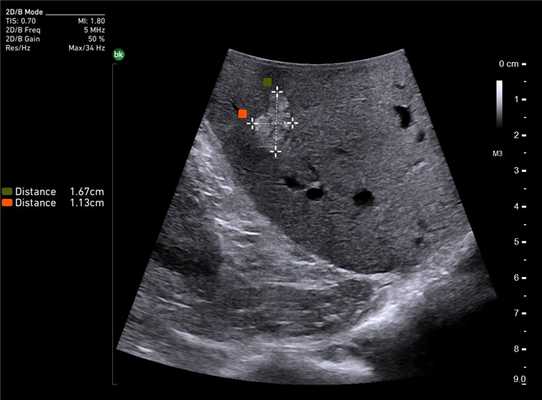

У 5 (41,7%) из 12 пациенток образования в печени имели гиперэхогенную, гомогенную структуру с четкими и ровными контурами размером от 5 до 12 мм в диаметре, которые были интерпретированы как доброкачественные образования печени — гемангиомы (табл. 2). У 4 (33,3%) пациенток образования имели анэхогенную гомогенную структуру, с четкими и ровными контурами, с гладкой внутренней выстилкой и эффектом усиления эхосигнала, размером от 3 до 11 мм в диаметре, и были интерпретированы как кисты. В 3 (25%) случаях в печени были выявлены гипоэхогенные образования солидной гетерогенной структуры с нечеткими, но ровными контурами размером от 10 мм в диаметре (рис. 1) до 22×17×15 мм в одном случае, расположенное на диафрагмальной поверхности печени, которое «самоампутировалось» в процессе исследования и при срочном гистологическом исследовании оказалось метастазом аденогенного рака (рис. 2).

Клинический пример N2. Пациентка Р. находилась на лечении в ГУРОНЦ РАМН. При прохождении обследования был установлен диагноз рак толстой кишки. По данным ультразвуковой компьютерной томографии на фоне выраженной диффузной неоднородности паренхимы печени очаговые образования не определялись. При проведении ангиографии и компьютерной томографии так же убедительных данных за наличие метастазов в печень получено не было. При интраоперационном ультразвуковом исследовании были выявлены два очага, характерными особенностями которых являлись малые размеры (0,2 - 0,4 см), а так же нечеткость контуров и изоэхогенность структуры (рис. 1 а,б).

Рис. 1. Метастатические очаги (стрелки) в печени при интраоперационной ультразвуковой томографии.